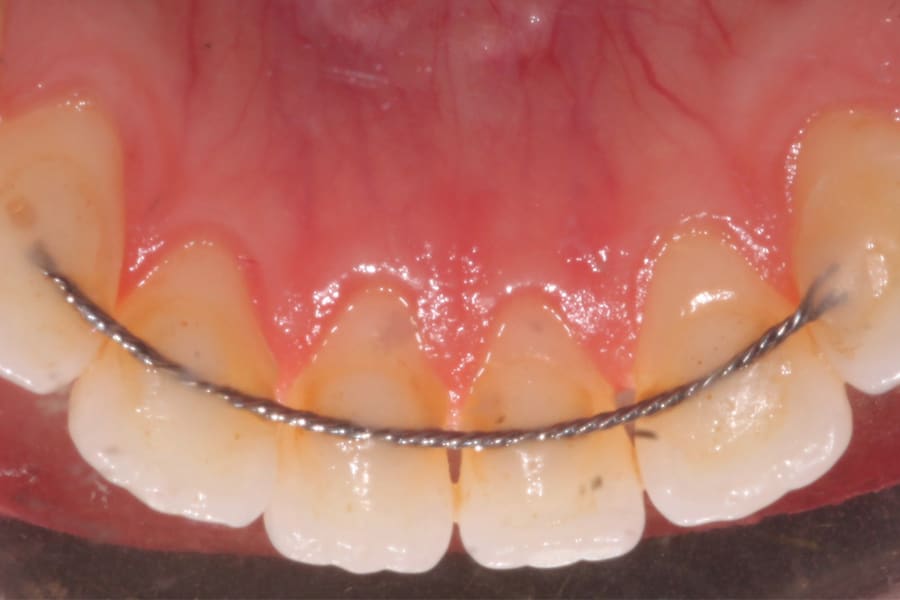

A popular example of this approach is the twisted stainless-steel wire retainer (Figure 1). This design features ease of fabrication and placement as well as minimal cost. Frequently, a twisted lingual retainer can be fabricated chairside and placed immediately with no preparation, impressioning, or laboratory fabrication required. Consequently, this design is commonly utilized. It can be made from a very thin wire (such as a .009" ligature tie) that is folded over and spun down (or twisted) then formed to the arch curvature and direct bonded. Annealing the formed wire prior to placement can be beneficial, as this can remove the "memory" that stainless steel possesses if not permanently deformed.

Obviously, more suitable and reliable fixed lingual retention designs are needed, and, fortunately, many are available. As described above, the twisted chairside fabricated design can be unreliable. A well-suited alternative is a passive braided design as shown in Figure 2 (Ortho FlexTech® stainless steel, Reliance Orthodontics, relianceorthodontics.com). The braided design does not uncoil over time. The lingual retainer is placed in passive fashion after being cut to the proper length from a spool and bonded to the appropriate teeth. This relatively inexpensive alternative is fabricated chairside with no laboratory intervention or special preparation required. One potential downside is that it is a relatively bulky option.